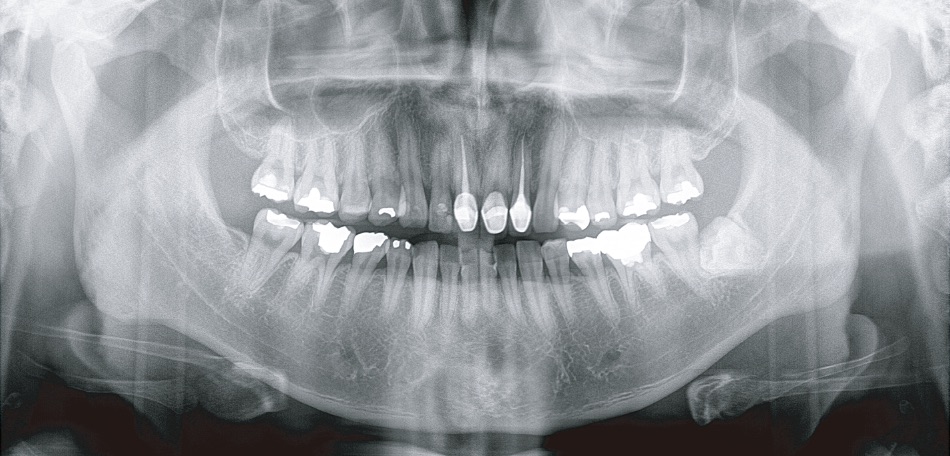

顎骨直交パノラマ撮影